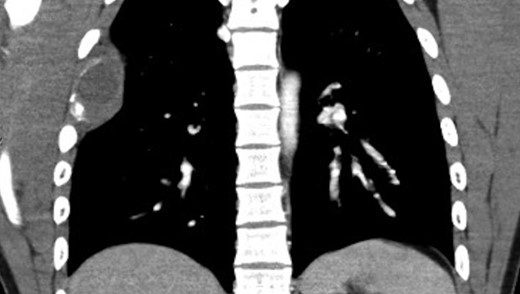

Chest x-ray revealed a destructive lesion in the posterolateral right fourth rib with associated soft tissue component consistent with FD. A CT of the chest revealed cortical thickening and ground-glass appearance of the right fourth rib (Fig. 3). A lytic lesion was noticed in the posterolateral fourth rib with a soft tissue component and cortical thinning adjacent to the area of FD appeared consistent with ABC. MRI of the chest revealed a 7 cm × 3 cm complicated cystic lesion within the right fourth rib with fluid levels consistent with ABC (Fig. 4). The skull lesion represented the most accessible site for biopsy and possible excision. For completeness, a bone scan was performed to evaluate other areas of involvement and remarkably the scan revealed increased uptake in the right frontal region, right fourth rib and in the right upper extremity. X-rays of the right upper extremity revealed non-expansile ground-glass process within the humerus and proximal one-third of the radius consistent with a history of FD with ABC formation (Fig. 5). The patient denied right extremity pain and was not tender to palpation along upper extremity.